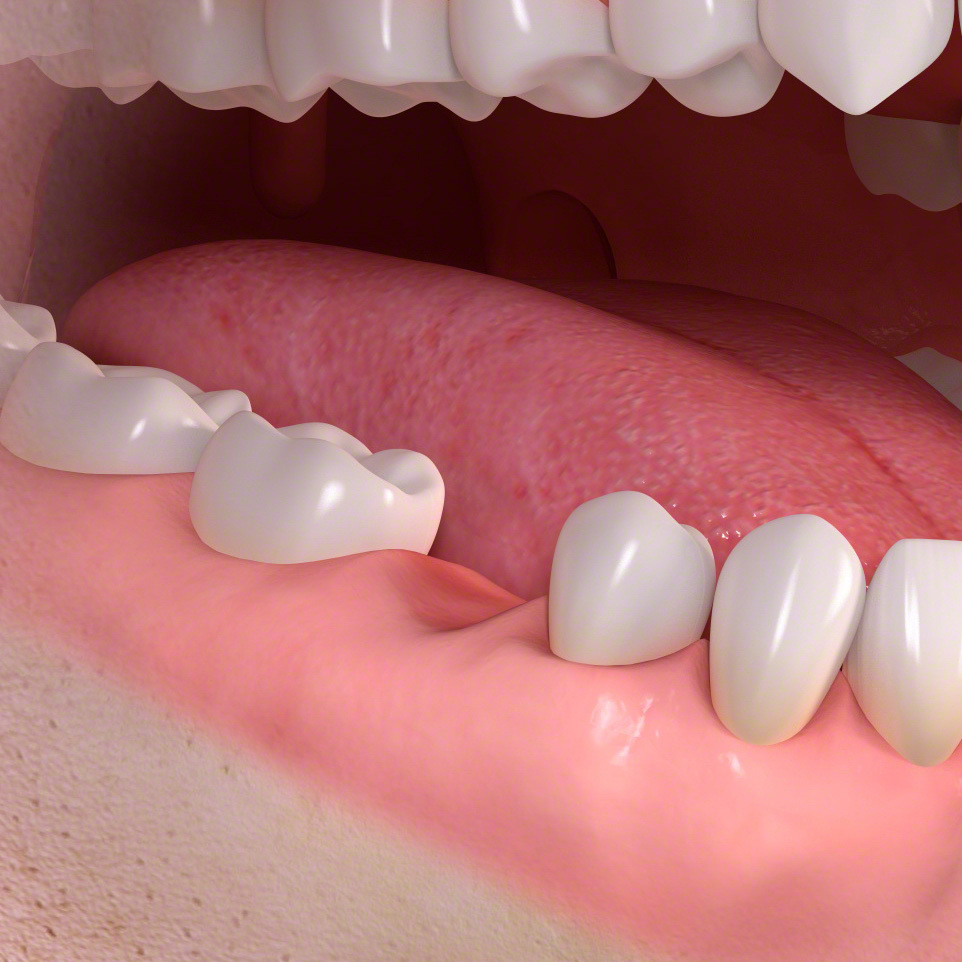

歯の欠損

ブリッジは少数の歯を失った時に行う治療法です。

前後の土台になる歯が平行に生えている場合のみ可能な治療法です。

ブリッジ準備

無い場所に歯を作るため前後の歯を平行に小さく削ります。

ブリッジ

3本つながった歯の被せ物をセメントで固定します。

保険の場合、奥歯は銀歯になります。

白い歯をご希望の場合は自費のセラミックになります。